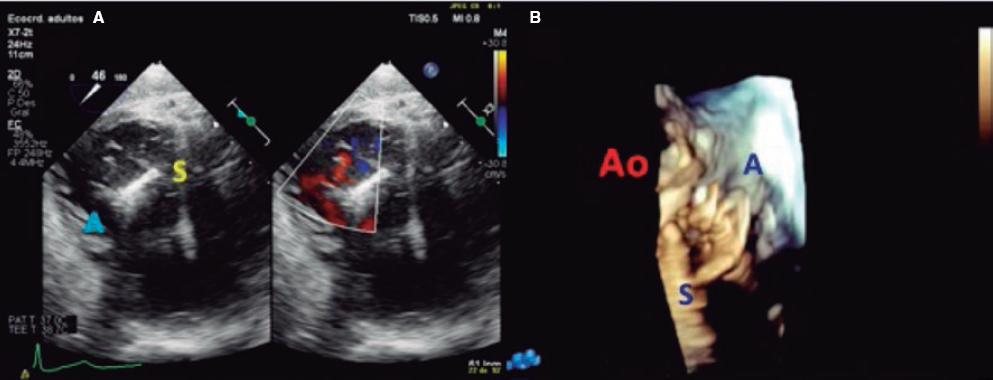

2. Mid-esophageal view of the RV inflow and outflow tract (intercommissural tricuspid view) between 60° and 90°. It shows the imaginary line from the anteroseptal (A-S) commissure up to the posteroseptal (P-S) commissure. The anterior leaflet close to the aorta and the posterior leaflet on the lateral side can be seen (video 1 of the supplementary data). This is the reference view to obtain biplanar images for the assessment of the septal leaflet. By bringing the cursor close to the aorta (X-plane tool), the orthogonal view shows the A-S coaptation and the anterior and septal leaflets. By moving it away from the aorta towards the lateral position, the view shows the P-S coaptation and the posterior and septal leaflets. The same views should be acquired using the Doppler color technique (figure 2) to see whether the origin of the regurgitant jet is of anterolateral or P-S predominance.

Figure 2. Intercommissural mid-esophageal view. A: when placing the cursor next to the aorta, the orthogonal view shows the anteroseptal coaptation line. B: by moving the cursor towards the most lateral region, the orthogonal view is acquired showing the posteroseptal coaptation line. C and D: color biplanar imaging showing the origin of regurgitation jet. A, anterior; P, posterior; S, septal.

Also, these views are useful to measure the length of the leaflets, see coaptation defects, assess the movement of the leaflets, and see the presence of strings that can make the procedure difficult. The presence of serious restrictions in the movement of the septal leaflet limits the performance of the procedure with the current device.

The most common strategy is to place a clip between the A and S leaflets and towards the TV most central region. To acquire the grasping view and see the A and S leaflets we should start at the intercommissural view and the multiplanar view, and the grasping view will often be found at around 160° (figure 4). Another option is to perform a TEE transducer sweep from 0° to 180° until finding a direct grasping view to actually see the leaflets and the clip with wide open arms. In any case, every patient should be handled individually since the TV has more anatomical variations than the mitral valve. Also, the angle between the intercommissural view and the coaptation line of the A and S leaflets can be < 90º and mislead the multiplanar assumptions. The real-time 3D TEE can be useful to guide the clip, but not so much with mitral procedures.

Figure 4. Search for the grasping view for the clip in the anteroseptal (A-S) position with respect to the center of the tricuspid valve. A: grasping view for A-S clip (discontinuous blue line). B: transesophageal echocardiogram (TEE) at 160° showing the clip with wide open arms and the anterior and septal leaflets resting on them.